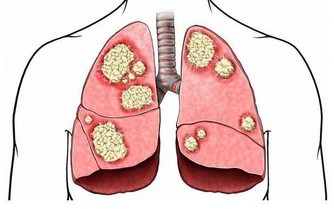

鱈魚富含的多烯脂肪酸具有防治心血管病的功效,而且還能抗炎、抗癌、增強免疫功能,對大腦發育、智力和記憶力的增長都有促進作用。

鱈魚肝含油量很高,對結核桿菌有抑製作用,肝油還可以消炎抗菌,所以用鱈魚肝油製作的油膏,可以促進傷口癒合。